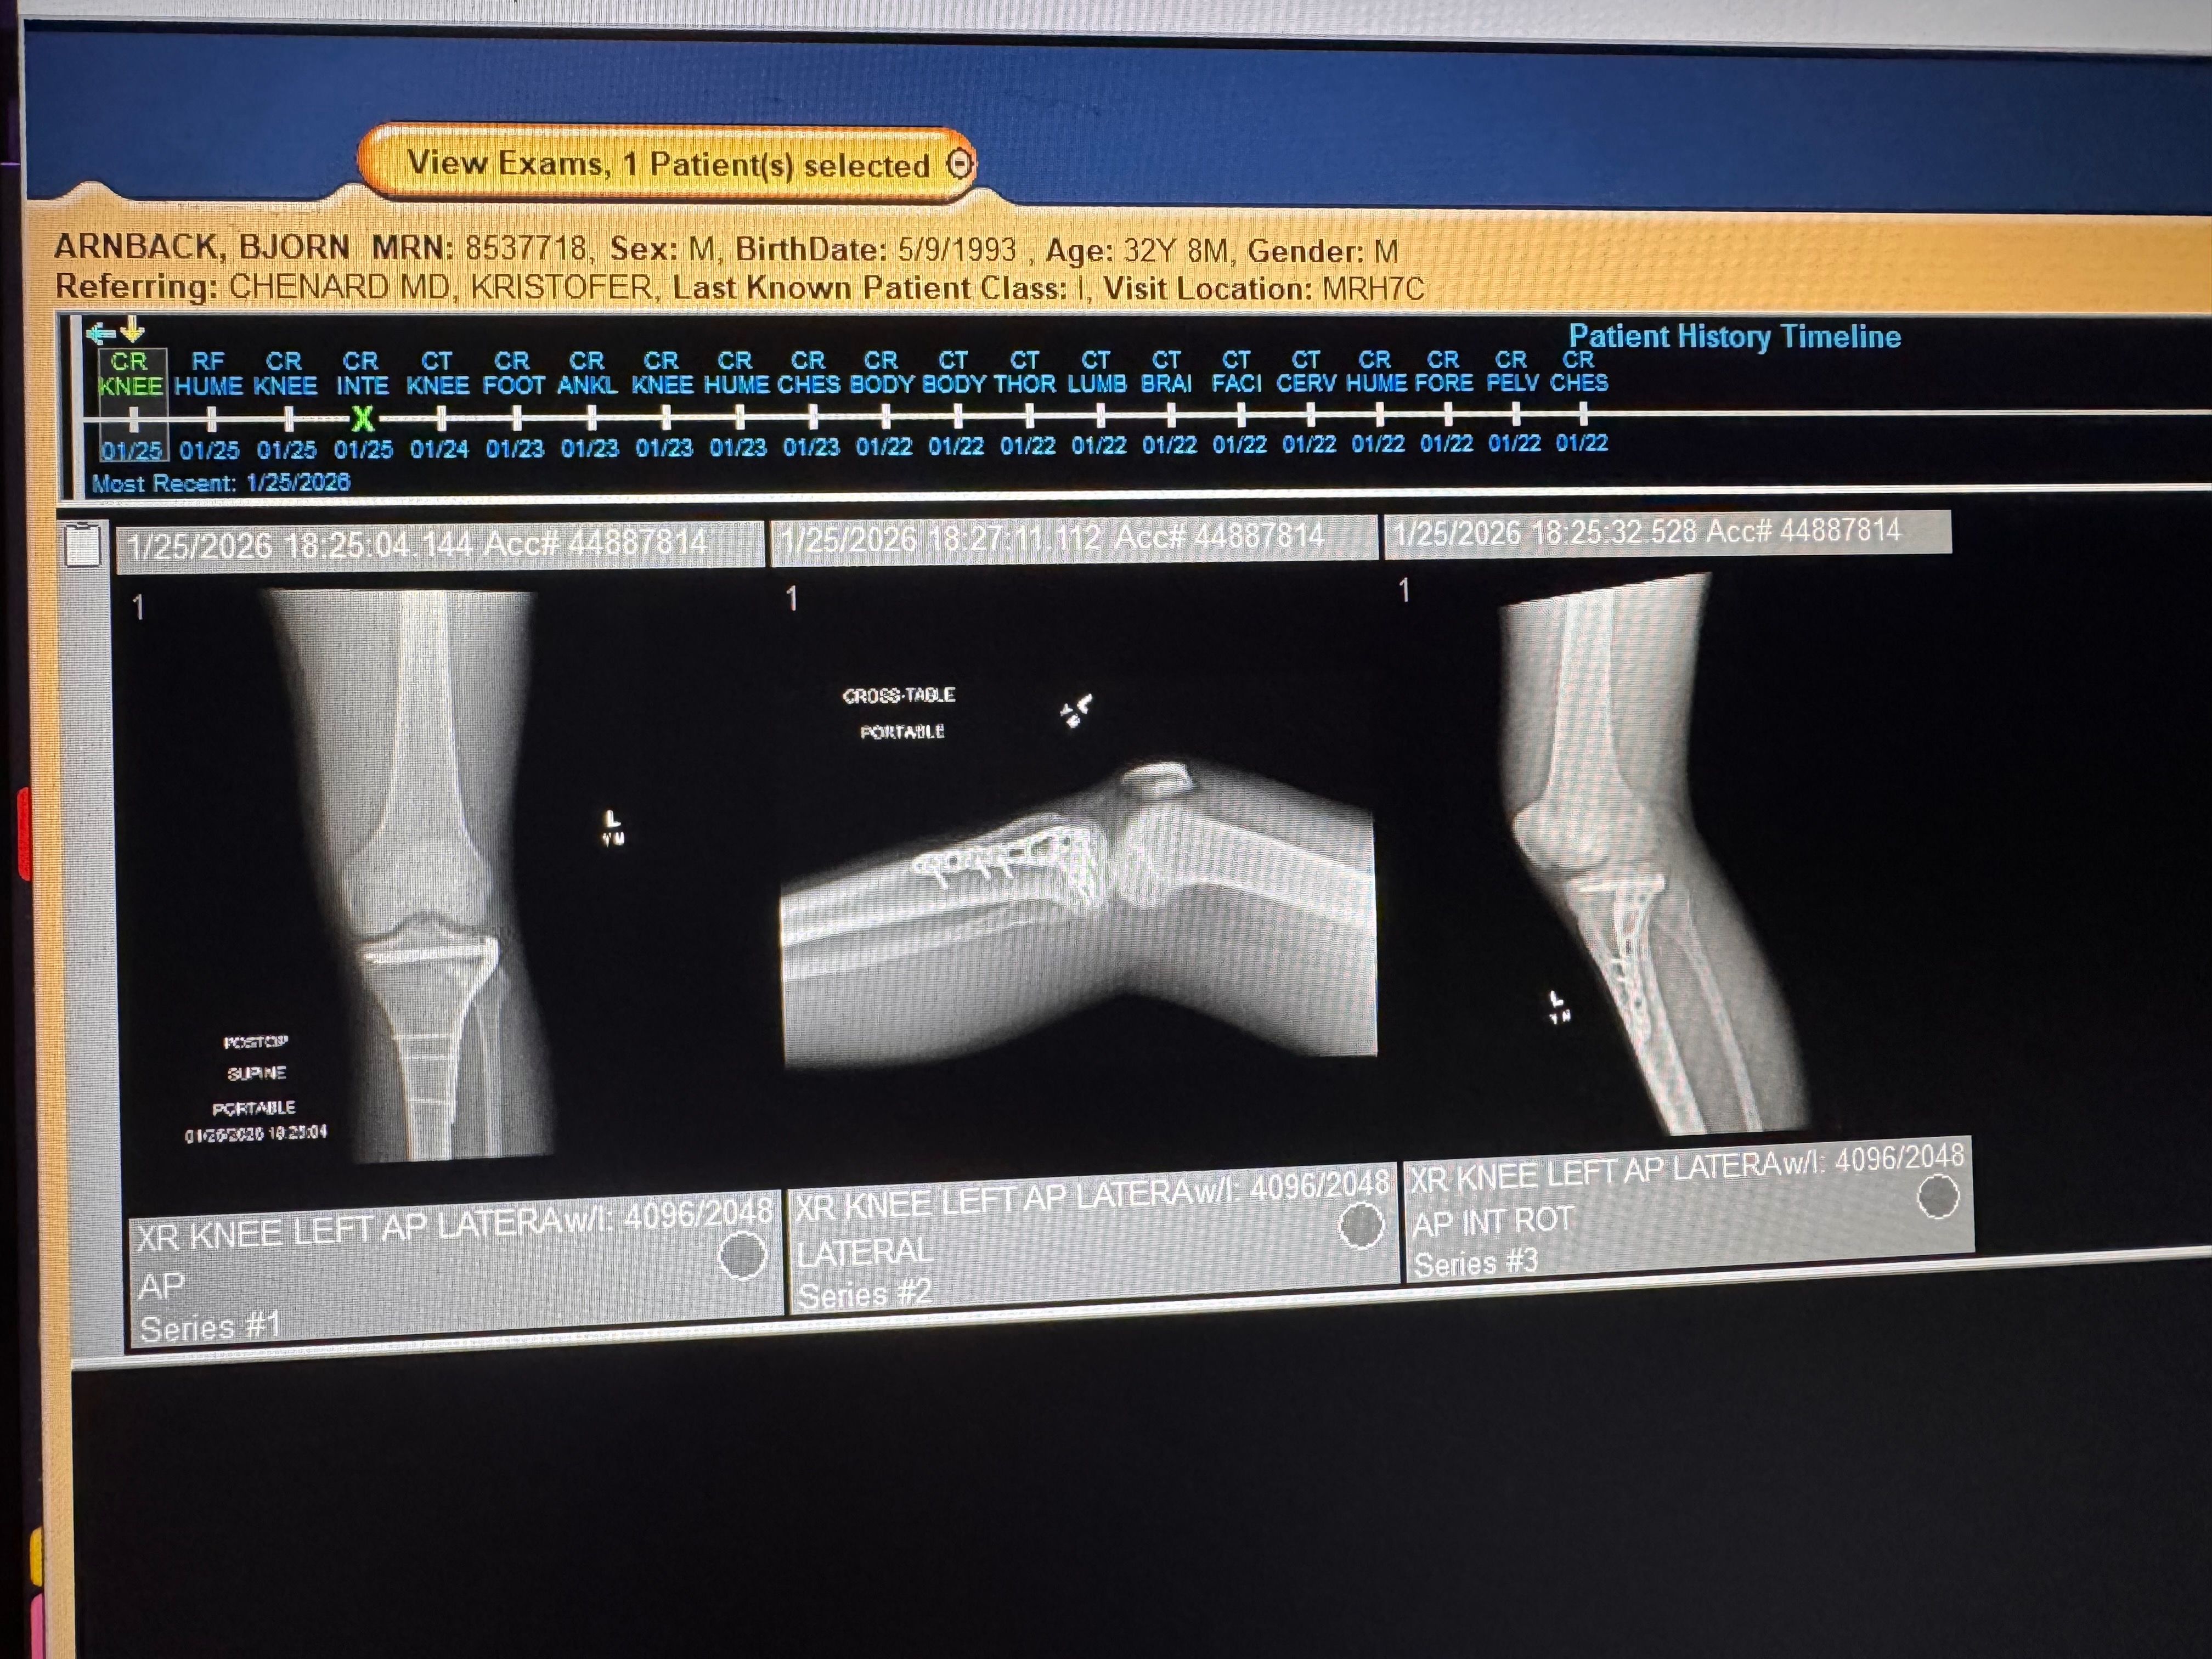

My name is Bjorn, and I’m reaching out because I recently experienced a life-changing motorcycle accident. In an instant, my world was turned upside down when I snapped my arm and broke my knee. The pain and shock were overwhelming, and I’m now facing a long and difficult recovery.